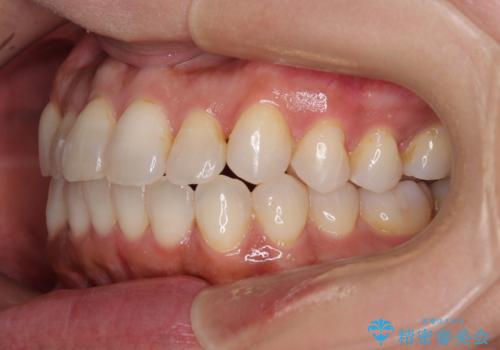

インビザライン特有の、治療後半に奥歯が咬み合わないという事象が長引きました。

咬み合わないときの対処方法は色々とありますが、ゴムかけなどを活用して噛めるようにしました。